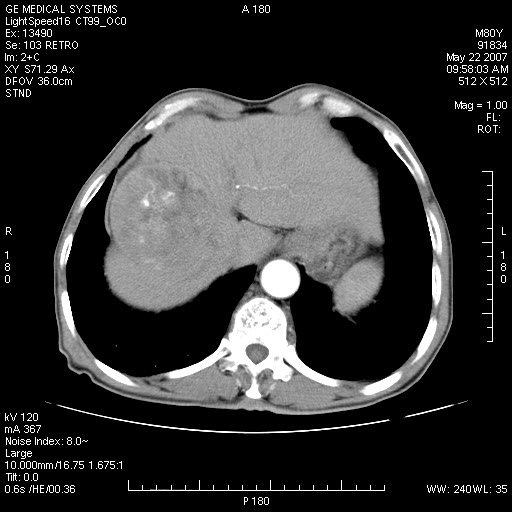

标题: CT8346:男,80岁。血尿,肝脏,膀胱占位,是否为肝转移?

男,80岁。血尿,无腹部不适病史。

肝脏病变:

膀胱病变:

增强原原发性肝癌、膀胱癌伴左侧盆腔淋巴转移。

肝脏内病灶有假包膜,增强扫描动脉期有动静脉瘘,有快进快出特点,考虑原发性肝癌。病灶内有裂隙样低密度影,以纤维板层样细胞癌可能性大。膀胱左侧乳头状占位,增强呈明显强化,左侧盆腔内有肿大淋巴结,结合有血尿病史,考虑膀胱癌左侧盆腔淋巴结转移。